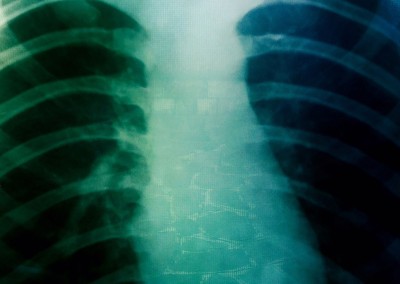

Copertina: dal Progetto Fotografico RESTART (2008-2024) – ReLate © Nazzareno Berton e Sergio Carlesso